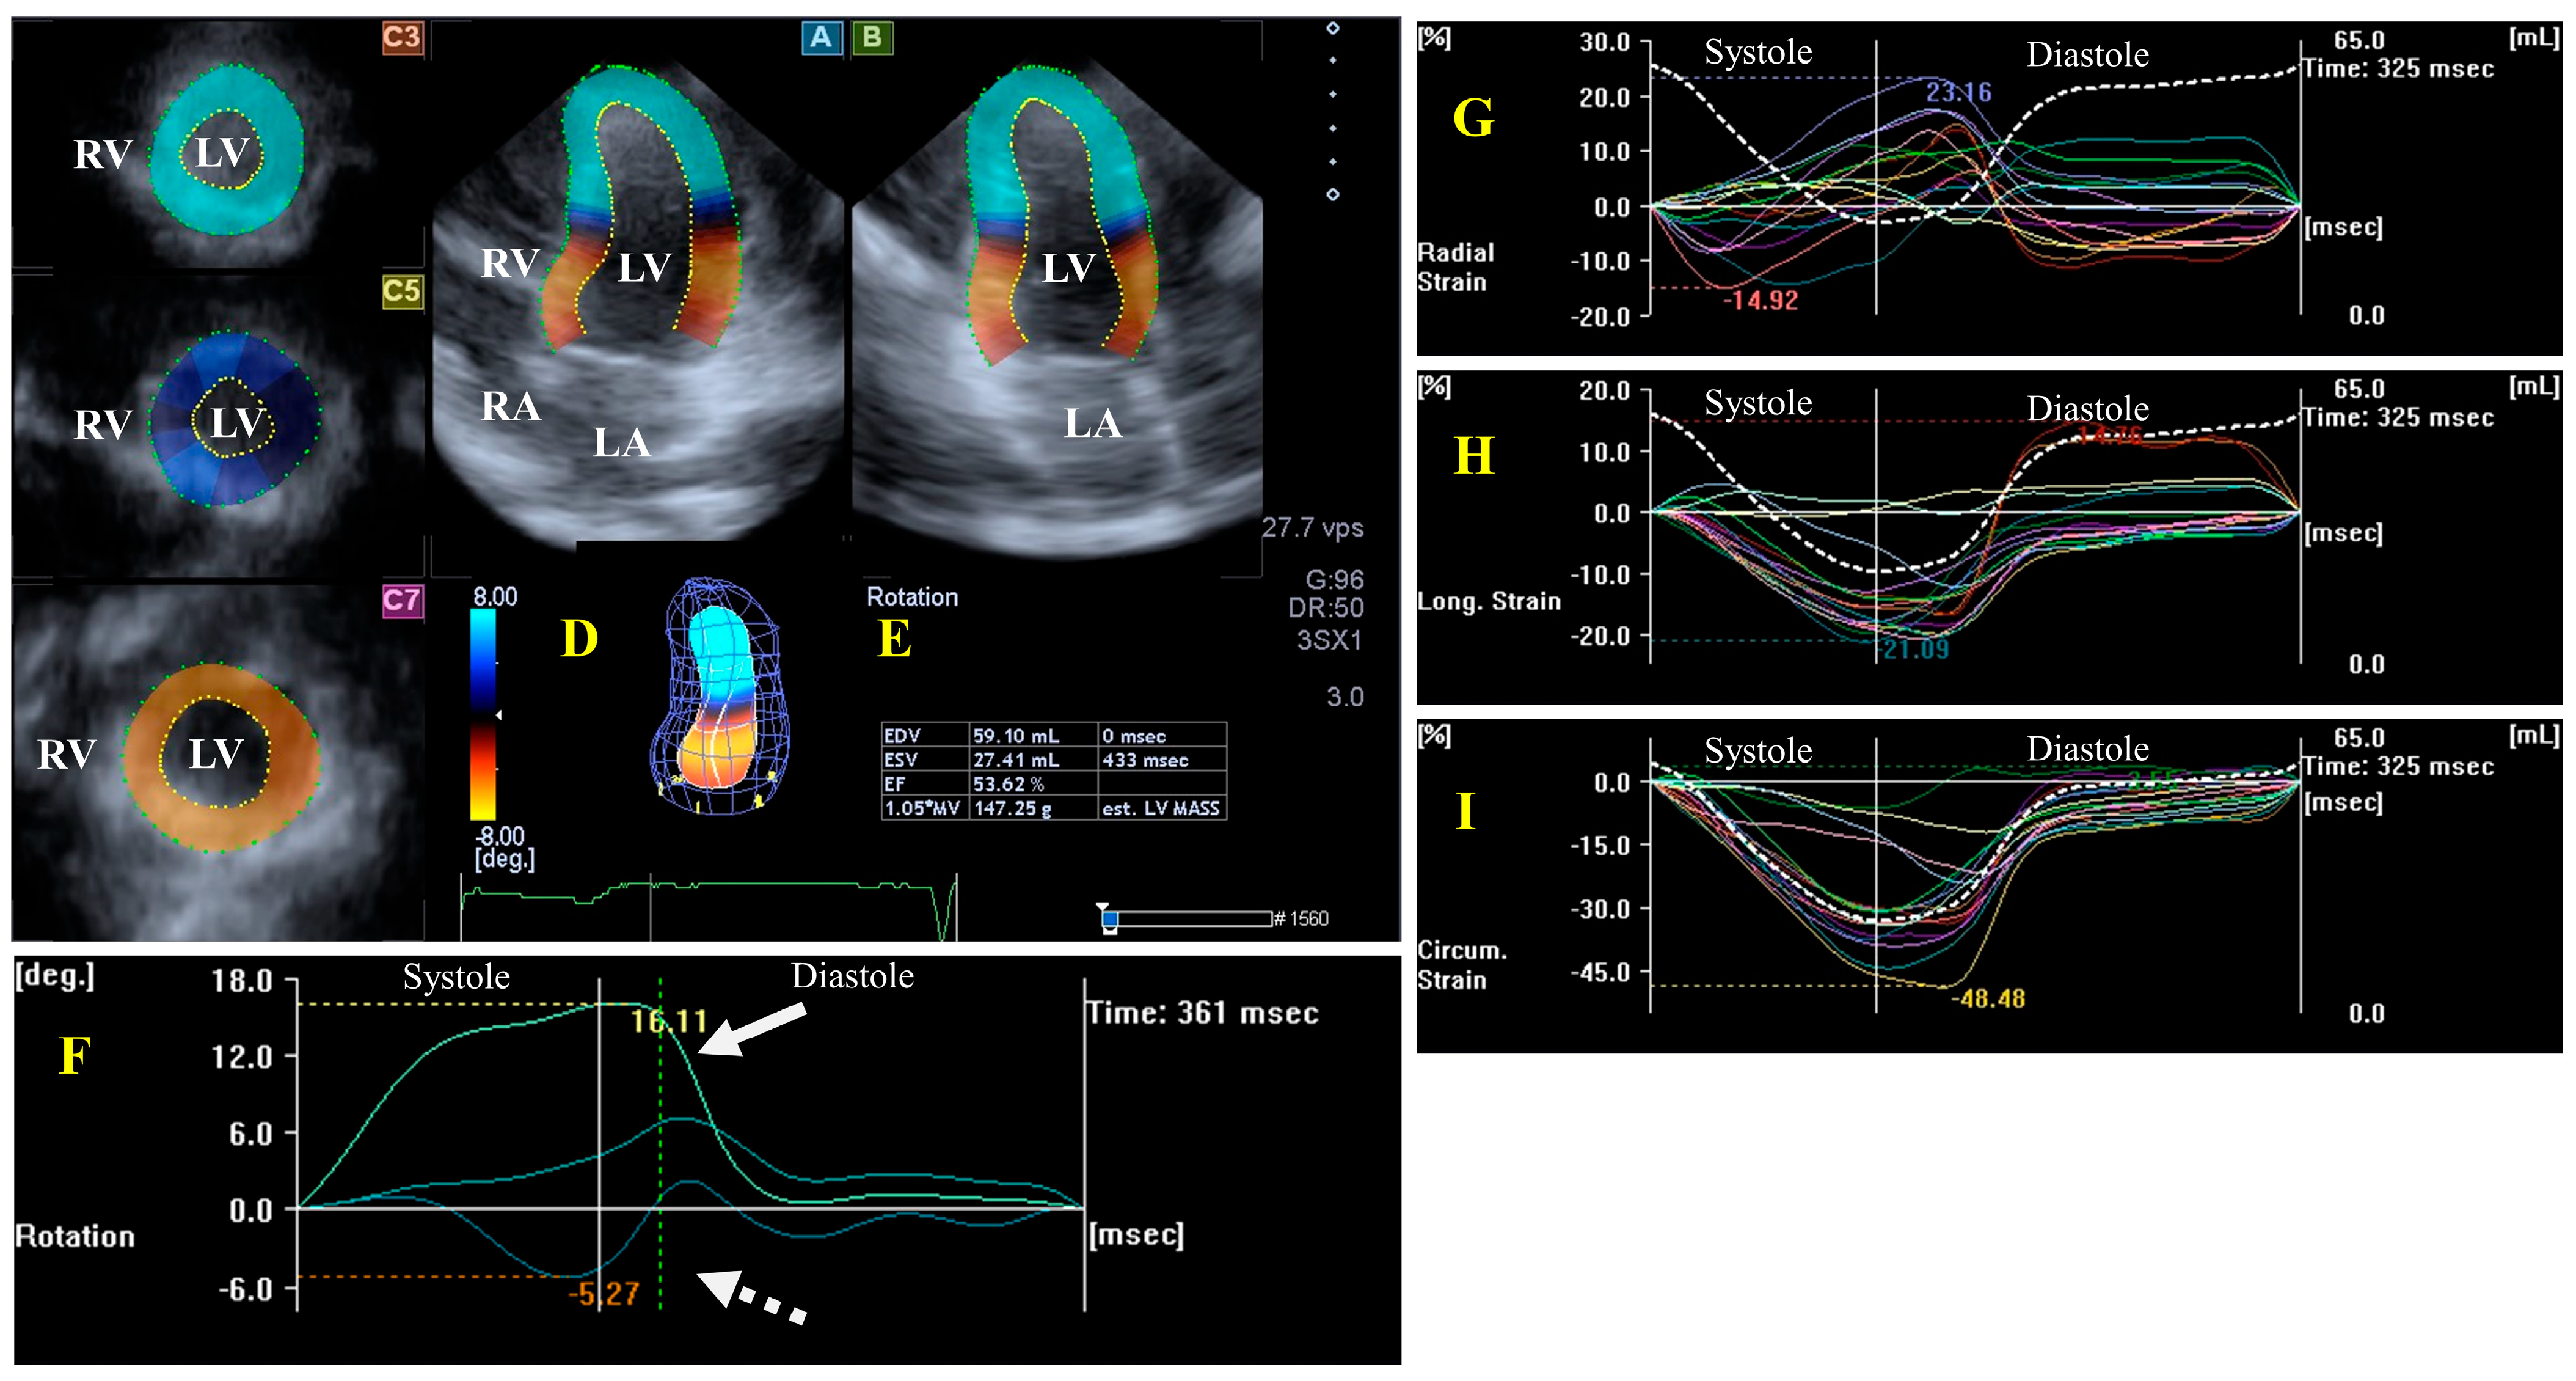

LV Functional Properties, Strains, and Rotational Mechanics

- Nemes, A.; Kormányos, Á.; Domsik, P.; Kalapos, A.; Ambrus, N.; Modok, S.; Borbényi, Z.; Marton, I. Left ventricular rotational mechanics in hypereosinophilic syndrome—Analysis from the three-dimensional speckle-tracking echocardiographic MAGYAR-Path Study. Echocardiography 2019, 36, 2064–2069. [Google Scholar] [CrossRef]

- Nemes, A.; Kalapos, A.; Domsik, P.; Marton, I.; Borbényi, Z.; Forster, T. Three-dimensional speckle-tracking echocardiography in Loeffler endocarditis: Case report from the MAGYAR-Path Study. Herz 2014, 39, 722–724. [Google Scholar] [CrossRef]

- Nemes, A.; Kormányos, Á. Prevalence of left ventricular ‘rigid body rotation’, the near absence of left ventricular twist (insights from the MAGYAR studies). Rev. Cardiovasc. Med. 2022, 23, 5. [Google Scholar] [CrossRef]